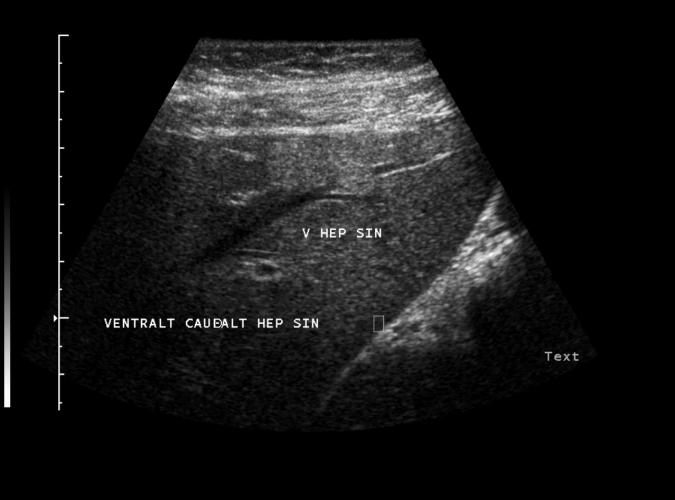

Patient med förhöjda leverprover. Hemangiom-liknande förändring ventralt i levern. Diagnosen bekräftades senare med kontrastförstarkt ultraljud.